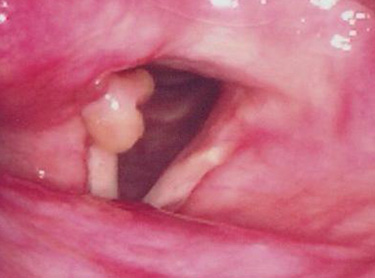

성대육아종은 접촉성 육아종과 삽관 육아종이 있습니다. 접촉성 육아종은 지나치게 낮은 톤으로 음성을 과도하게 사용하거나 만성적인 기침,

습관적 헛기침, 인후두 역류 등으로 발생하게 됩니다. 주로 남성에게서 발생하고 주증상은 애성과 인후두의 통증, 이물감 등을 호소하게 됩니다.

삽관 육아종은 후두수술이나 기관지경검사, 또는 기관내 삽관술 후에 잘 발생합니다.

주로 여자에서 발생하며, 피열연골의 성대돌기 부위의 점막손상이 생기고 이 손상 부위가 육아종으로 치유됩니다.

이 육아종은 처음에는 점점 커지지만 어느 정도 시일이 경과하면 퇴화하기 시작하고 양측성으로 오는 경우도 많습니다.